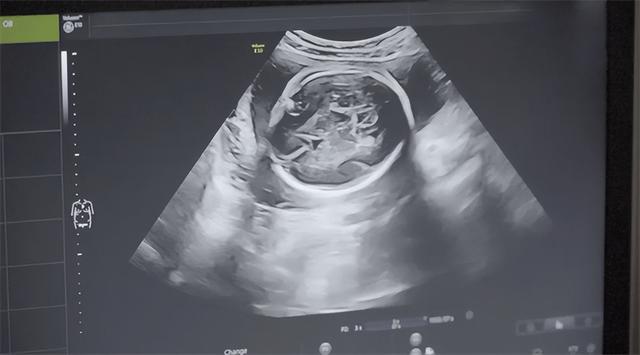

4个,整整4个孩子待在她的肚子里,只要一出生那就是4张嗷嗷待哺的嘴。

由不得王翠英不愁,医生告诉她,之前县里误诊了,她怀的孩子不是4个而是5个。